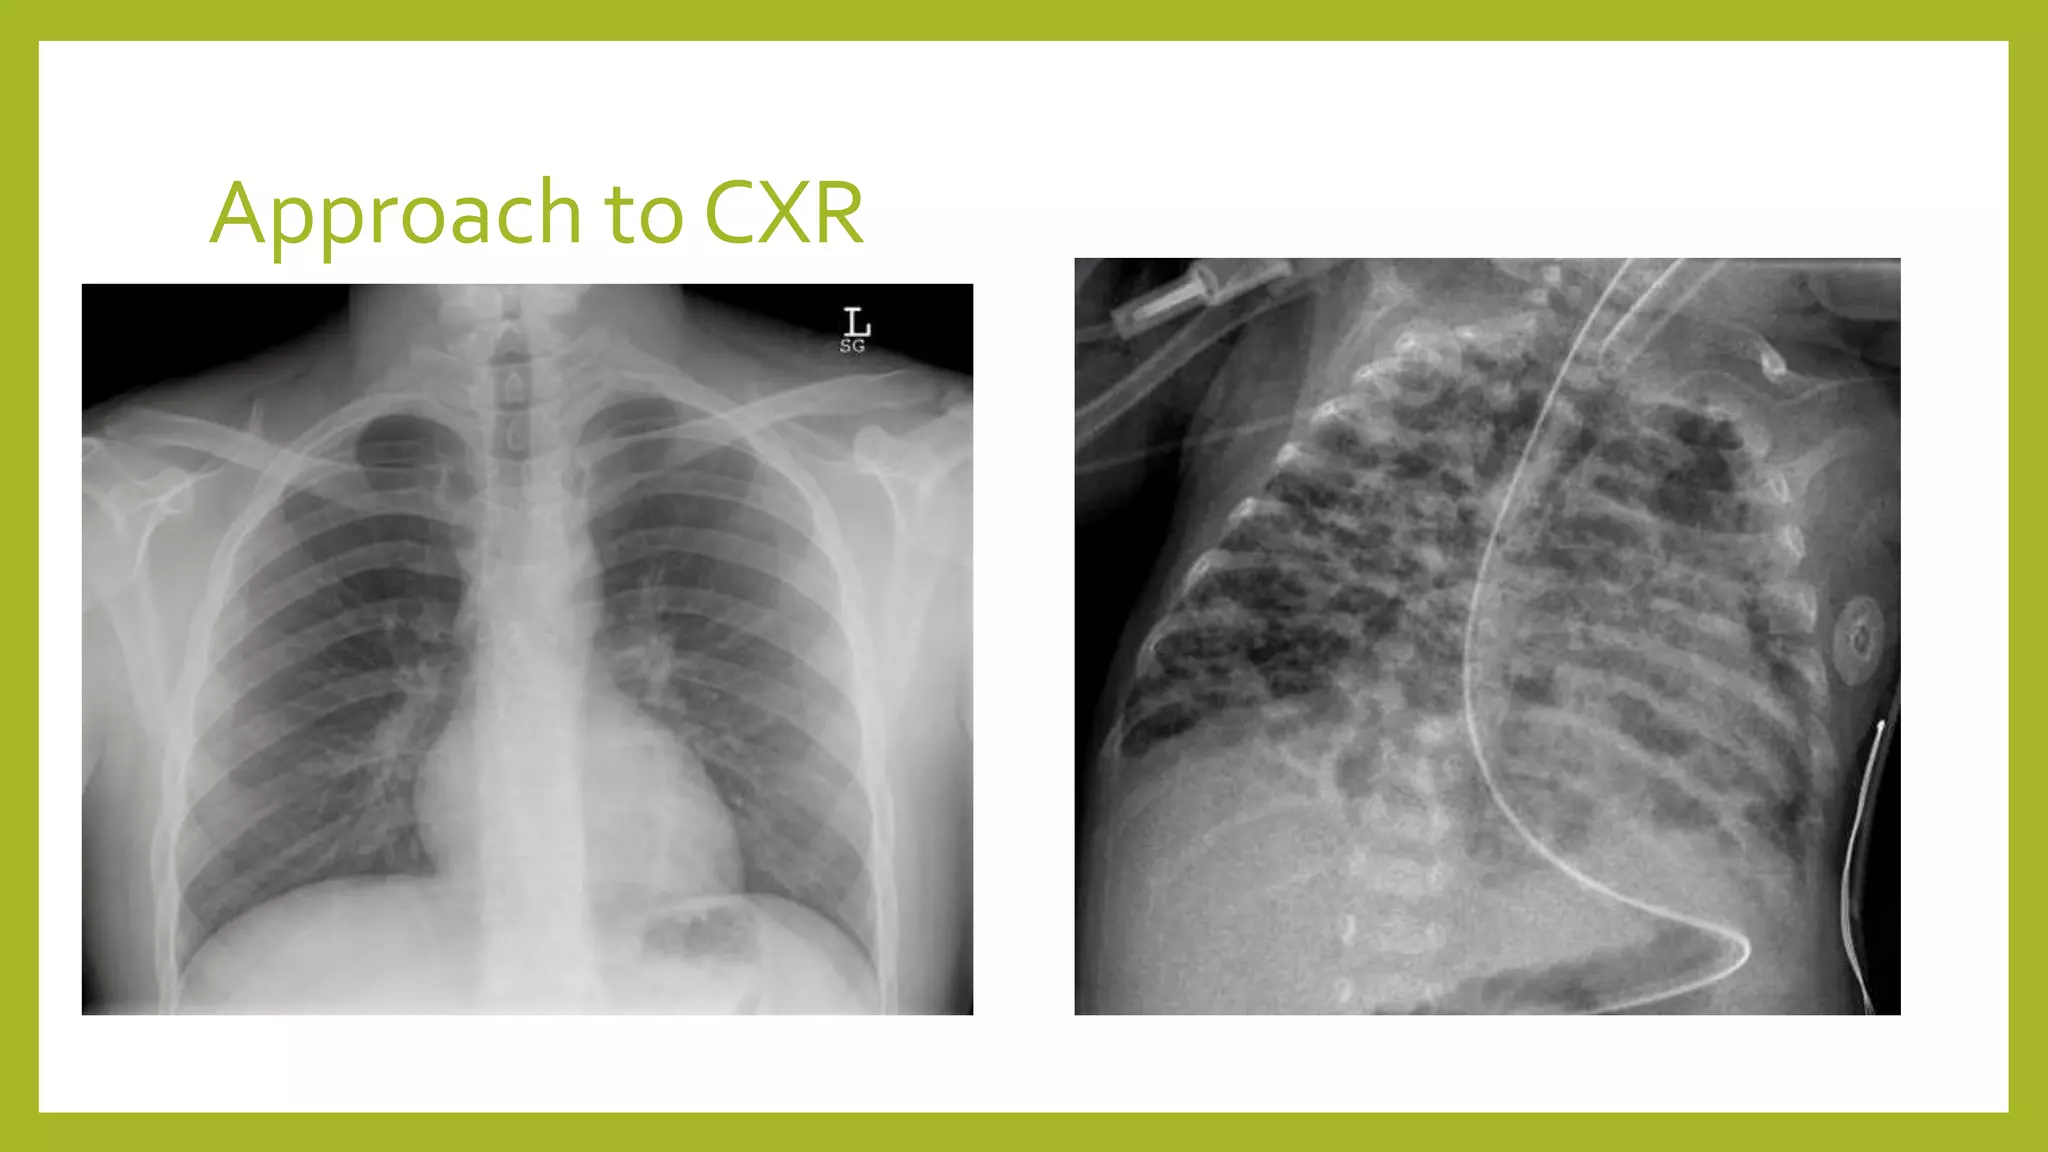

The document provides guidance on approaching and interpreting chest x-rays (CXR). It outlines steps to check the name, date and quality of the film, systematically scan the CXR looking for abnormalities, and determine if the lungs appear too white or black. Specific signs are described to help localize abnormalities, including the cardiac silhouette sign and pleural effusion signs. Examples are given of respiratory distress syndrome, tetralogy of fallot, transposition of great arteries, and total anomalous pulmonary venous return. The take home message is to summarize positive findings, compare to prior CXRs if available, and confirm findings with a radiologist.